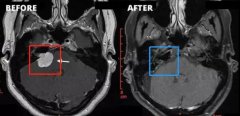

听神经瘤 是一种良性的,通常生长缓慢的肿瘤,由供应内耳的平...

听神经瘤 是位于内耳和大脑之间的平衡和听觉神经的肿瘤。肿瘤...